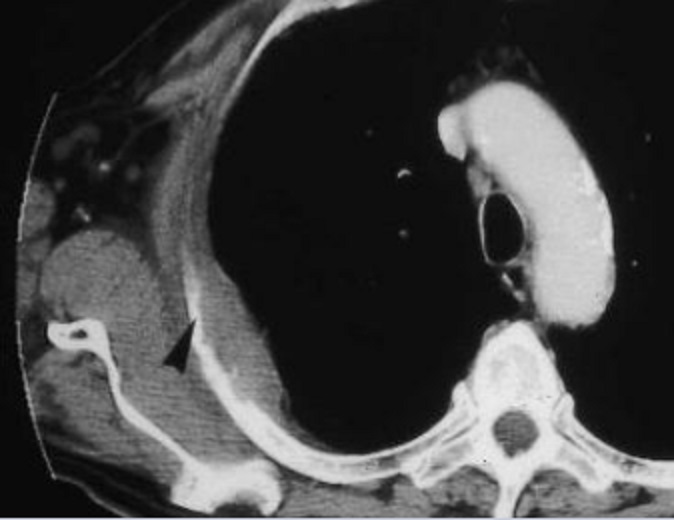

Même cas en coupe TDM axiale . Metastase

Syndrome pariétal avec lésion osseuse de hypodense

1/3 posterieure du cote droit (métastase

costale).

Image radiologique

TDM en coupe axiale |